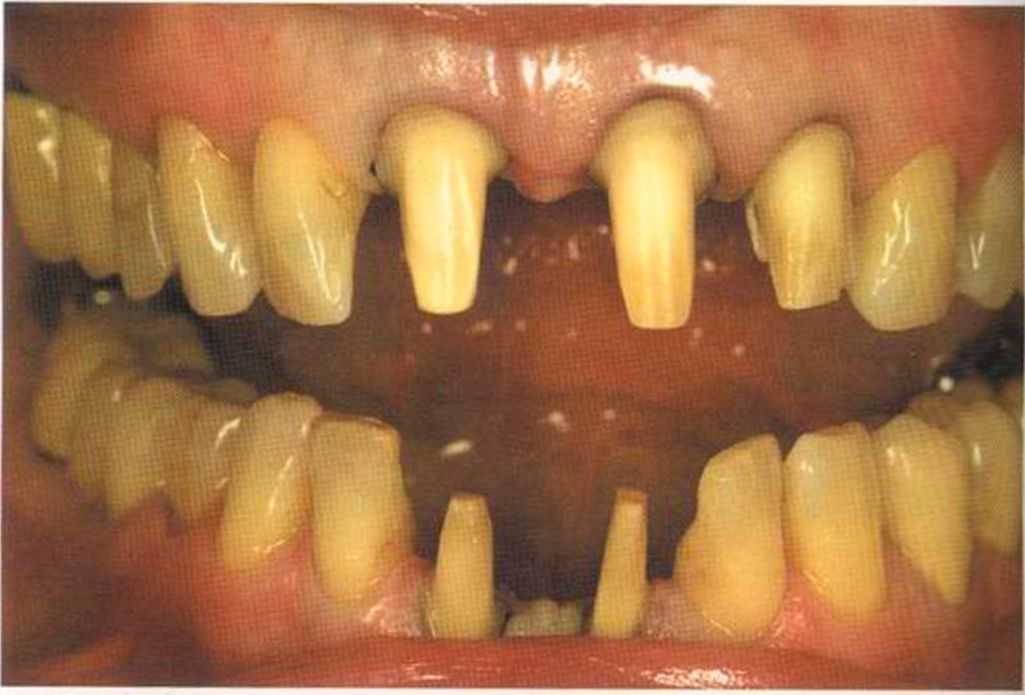

Эта женщина пришла в клинику доктора Лангханке с металлокерамической реставрацией.

Ей не нравились типичные в таких случаях темные края коронок и опаковость керамики.

Цвет 1М1 до 1М2 основной цвет в данном случае.